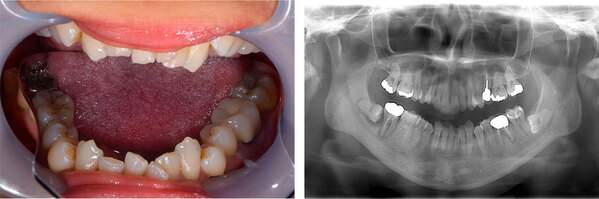

| 治療方針 | 5年ほど前に他院で治療した歯が噛むと痛いということでした。初診時のパノラマレントゲンを診てみると、根管治療がかなり雑にされており、その上にかぶせ物がはいっている状態でした。ですので、まずはかぶせ物をはずし、根管治療のやり直しを行います。 その後、感染物質を取り除くために、根尖切除も治療計画に含めました。根管治療のみで根の先の炎症がなくなれば根尖切除は行わない計画にしました。 |

| 治療内容 | 1. かぶせ物の除去 2. 感染根管治療 3. 1ヶ月経過観察 4. 咬合時にまだ違和感がある 5. 根尖切除 6. 半年経過観察 |

「左上の奥歯に違和感がある」という悩みを持たれている患者様が来院されました。虫歯部分を除去すると歯の神経に届いていましたので、歯の神経を守るために根管治療を行いました。

「右下奥歯が痛くて腫れている。」という悩みを持たれている患者様が来院されました。